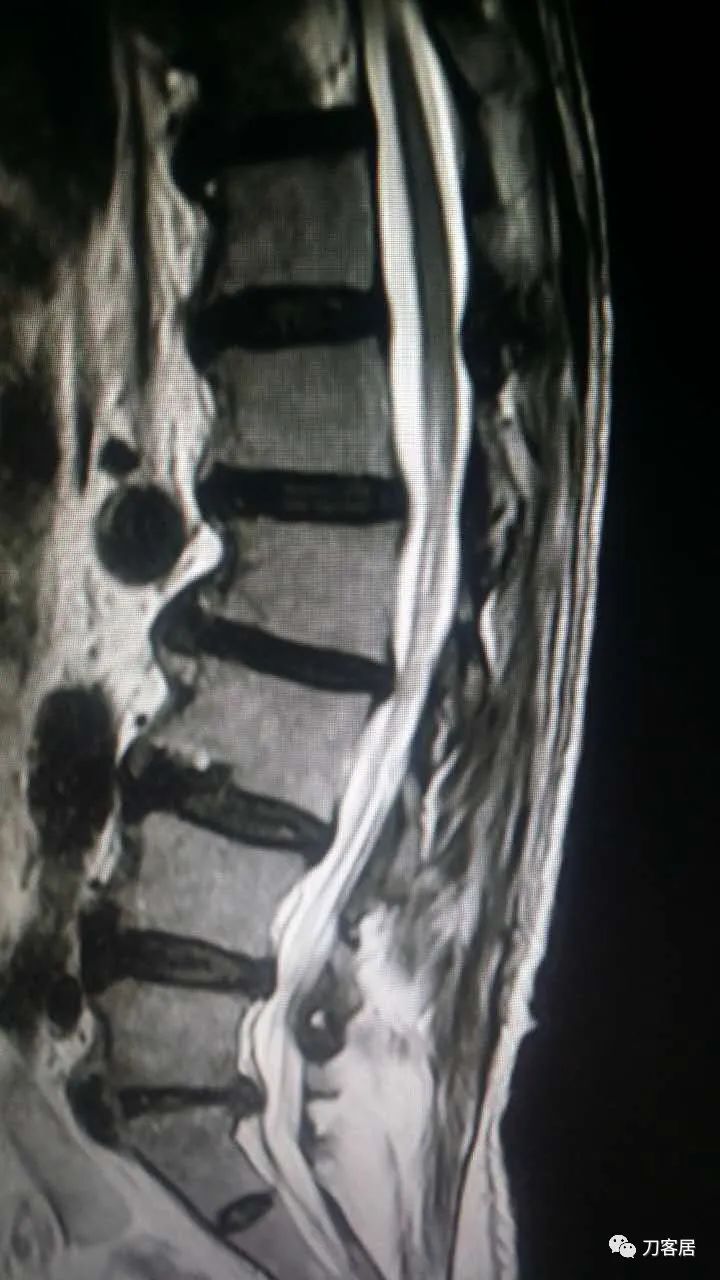

加注图14. 胸9-10椎管内后方高信号占位病变,考虑血肿形成。

加注图15. 胸9-10椎管内后方高信号占位病变,考虑血肿形成。

加注图16. 胸9-10椎管内后方高信号占位病变,考虑血肿形成。

加注图17. 胸9-10椎管内后方高信号占位病变,考虑血肿形成。

胸椎管内也有血肿[流泪] ,我要奔溃了,T9中段到10也有,偏左侧。

是啊,很难理解了 , 怎么那么高位置还有,而且是对侧?现在怎么开[流泪] , 从哪侧?上腰段偏右侧,下胸椎偏左侧。